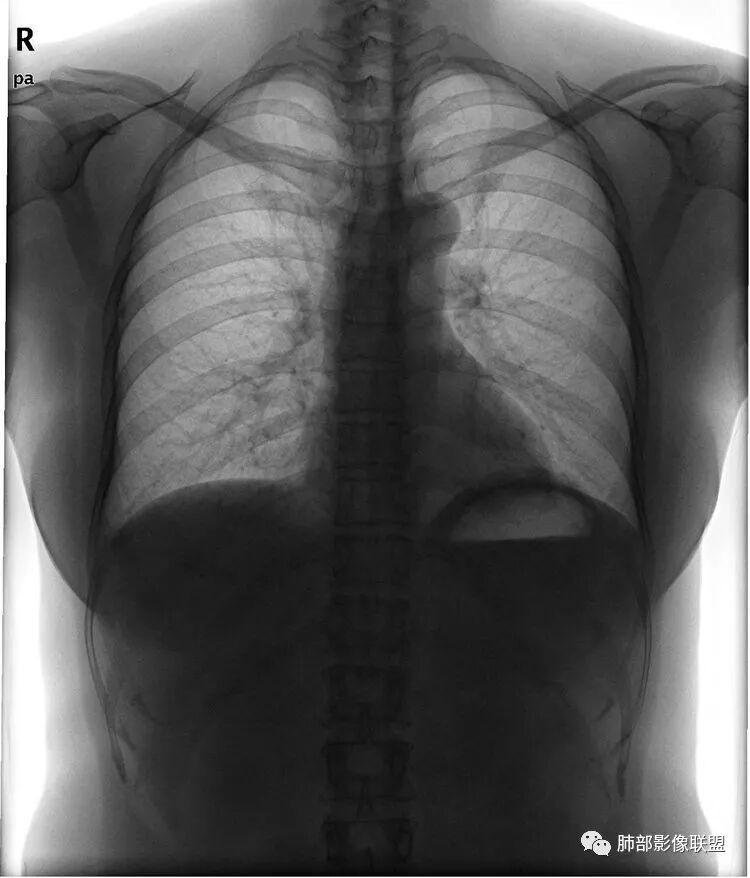

看似繁花似锦,也会暗流涌动。一张普通的胸片在基层很常见了,在一张看似正常的胸片后面隐藏了什么?敬请各位来分析。

Shelia:侧位心后间隙变小,下肺野与心影重叠区怀疑有斑片影

正位实在看不出什么问题

Coke with ice:唉……我都没找出来病变在哪……平片的老师们指点指点南边:

看完第二部分大家再说说看有什么体会?宇宙星空:左侧膈面上片状高密度影

M-Imaging :盘状不张不是,盘状不张,胖人腹压高多见远方:如南大所标示,标准答案。正位提示左肺下野与膈面重叠密度增高影,边缘光滑,侧位可再定位具体一点后肋膈角区密度增高影,具体是肺内肺外都有可能,盘状肺不张、肺内肿块、肺外病变(胸膜来源和膈肌来源)等都可以。我的体会常规正片再加负片结合这个肯定不会漏的,负片很有价值,平片发现问题就好,具体我们还是进一步CT检查了。

远方:基层医院很多都是X线为主,胸片占了一半以上,专科除外,正侧位片往往不重视侧位,临床医生也经常未要求侧位,考验我们影像医生了。这个单凭正位往往就漏了。恰好病变上缘与膈肌面比较重合。